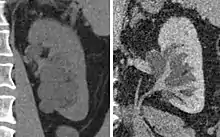

| Renal cyst of the left kidney (hyperintense area) as shown on MRI. | |